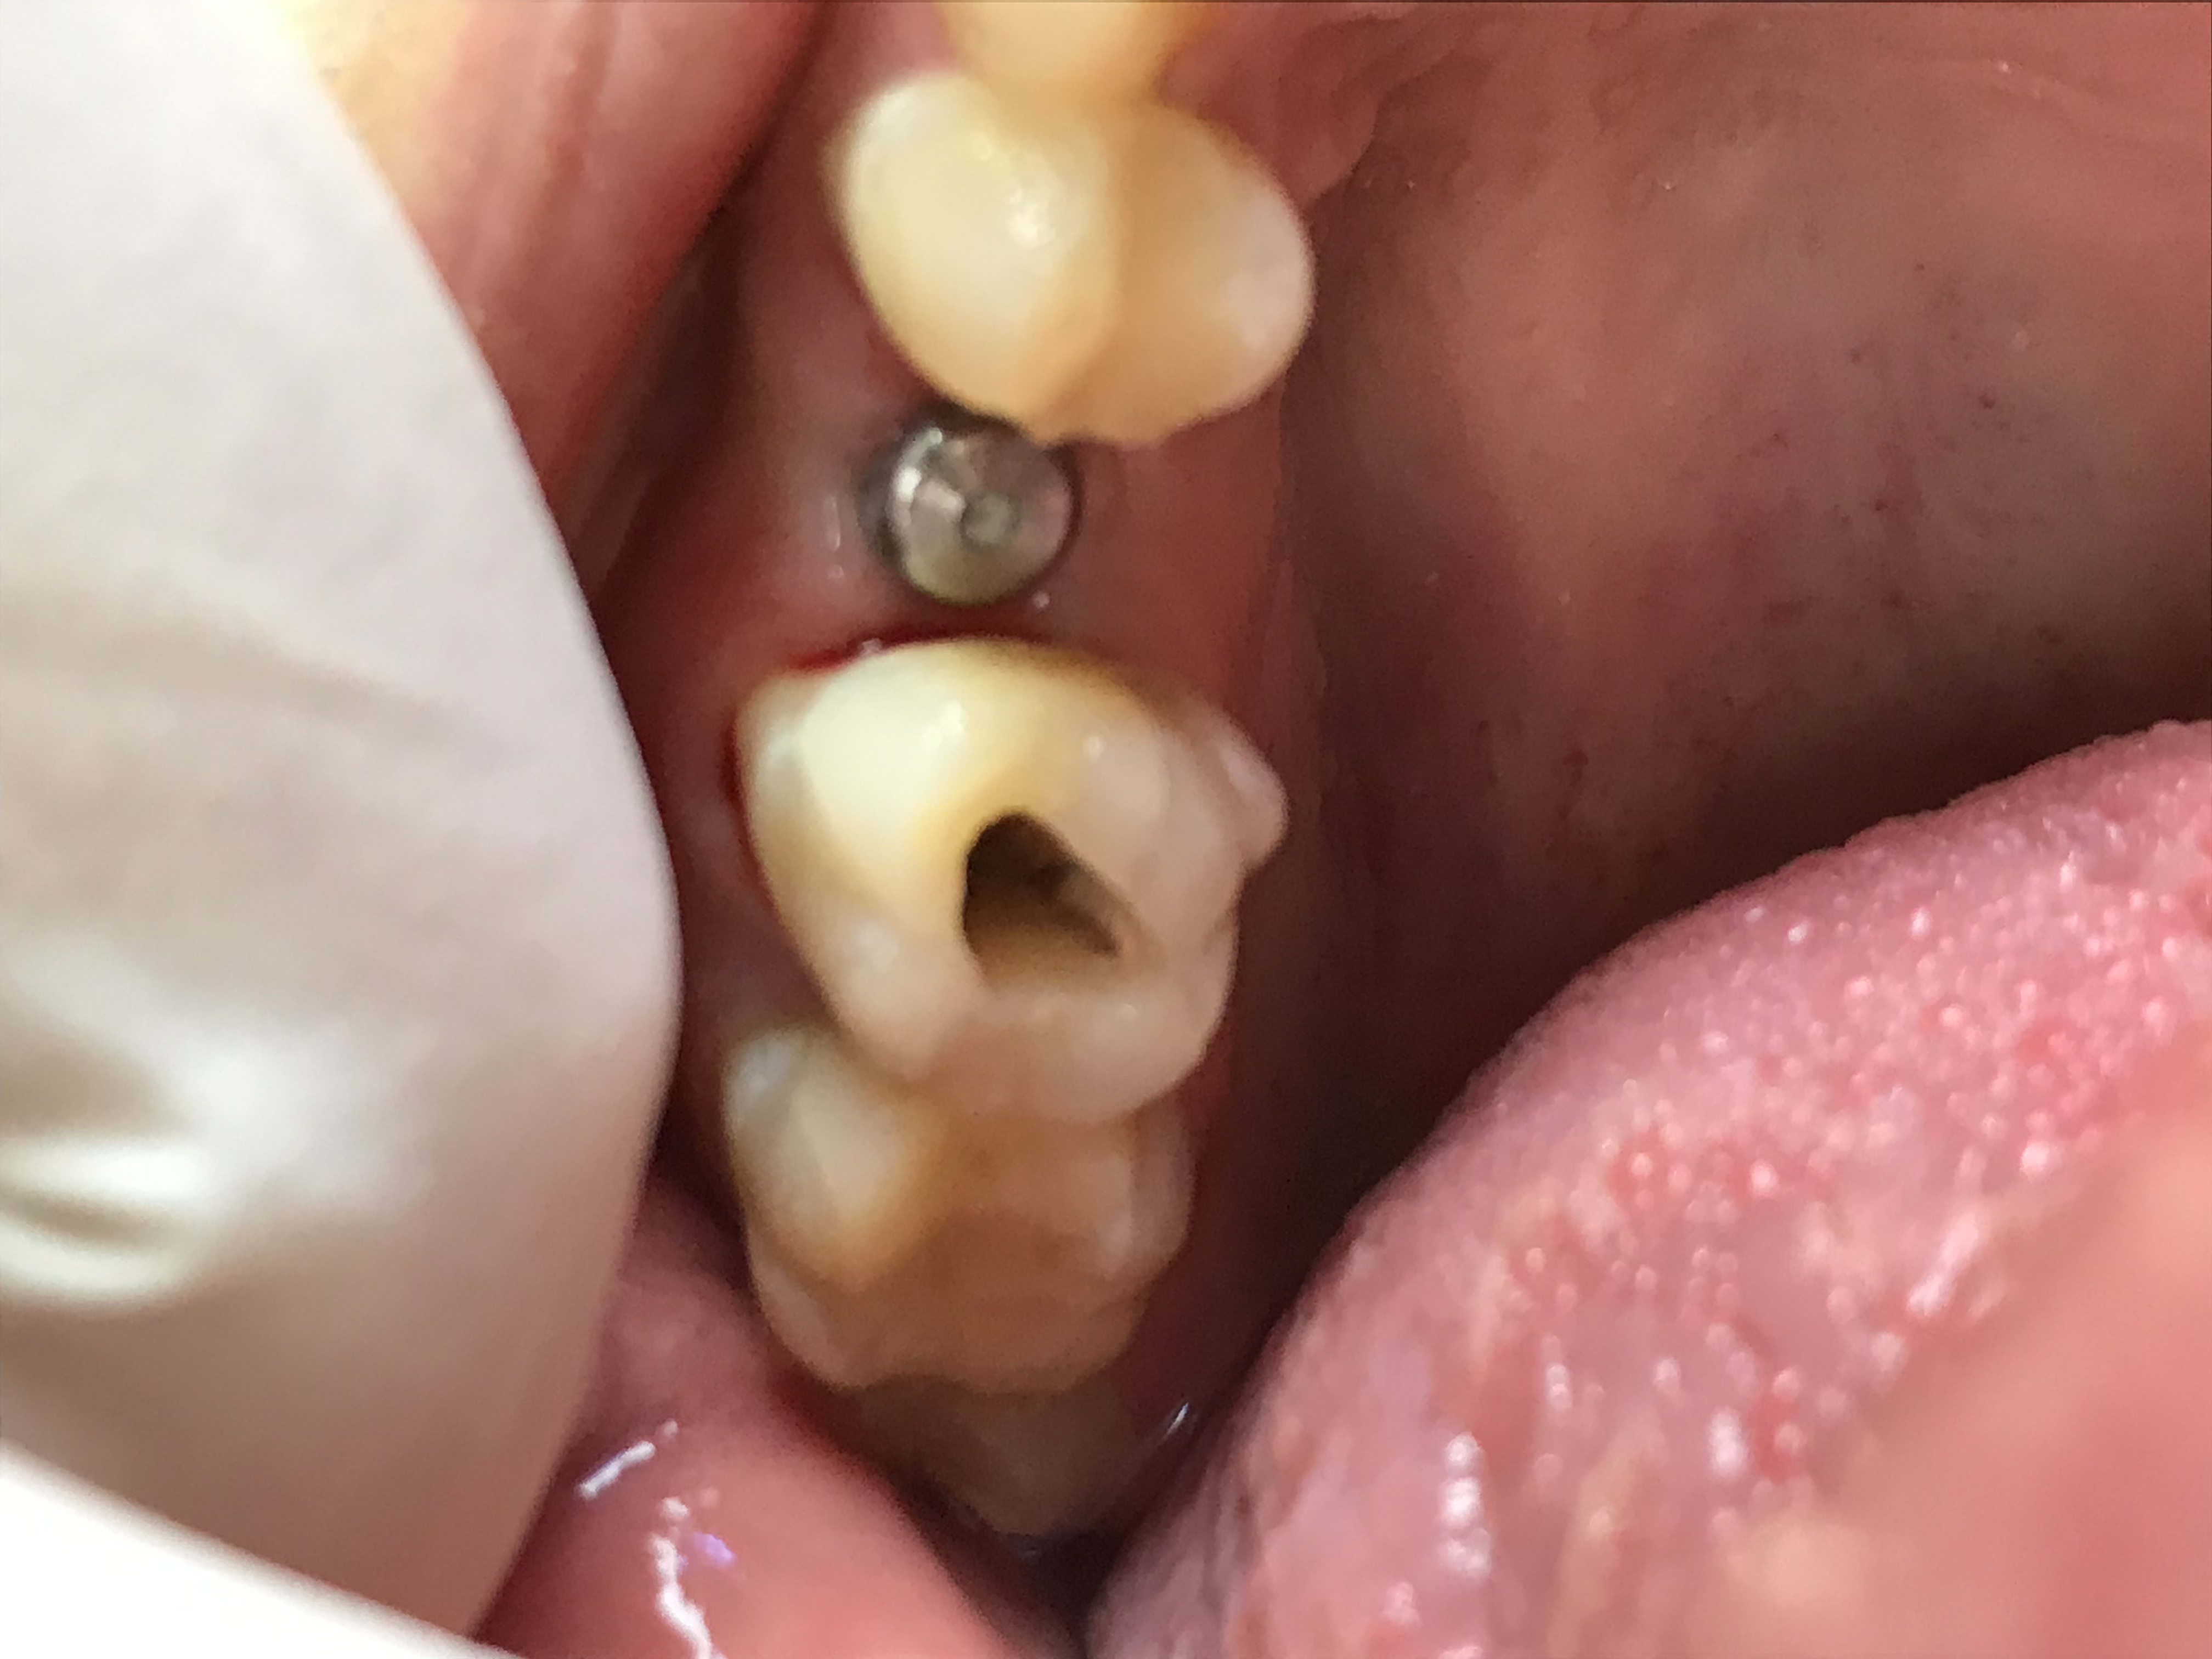

Nan vraiment c'est trop! Fallait pas (venir)...

Son "ex" m'a dit "depuis notre séparation ça a été la dégringolade pour lui"... C'est elle qui me l'a amené... Ah les femmes:-))

Dscf3286 ulx3ie - Eugenol

Dscf3287 ghd4mb - Eugenol

Dscf3288 lwxprq - Eugenol